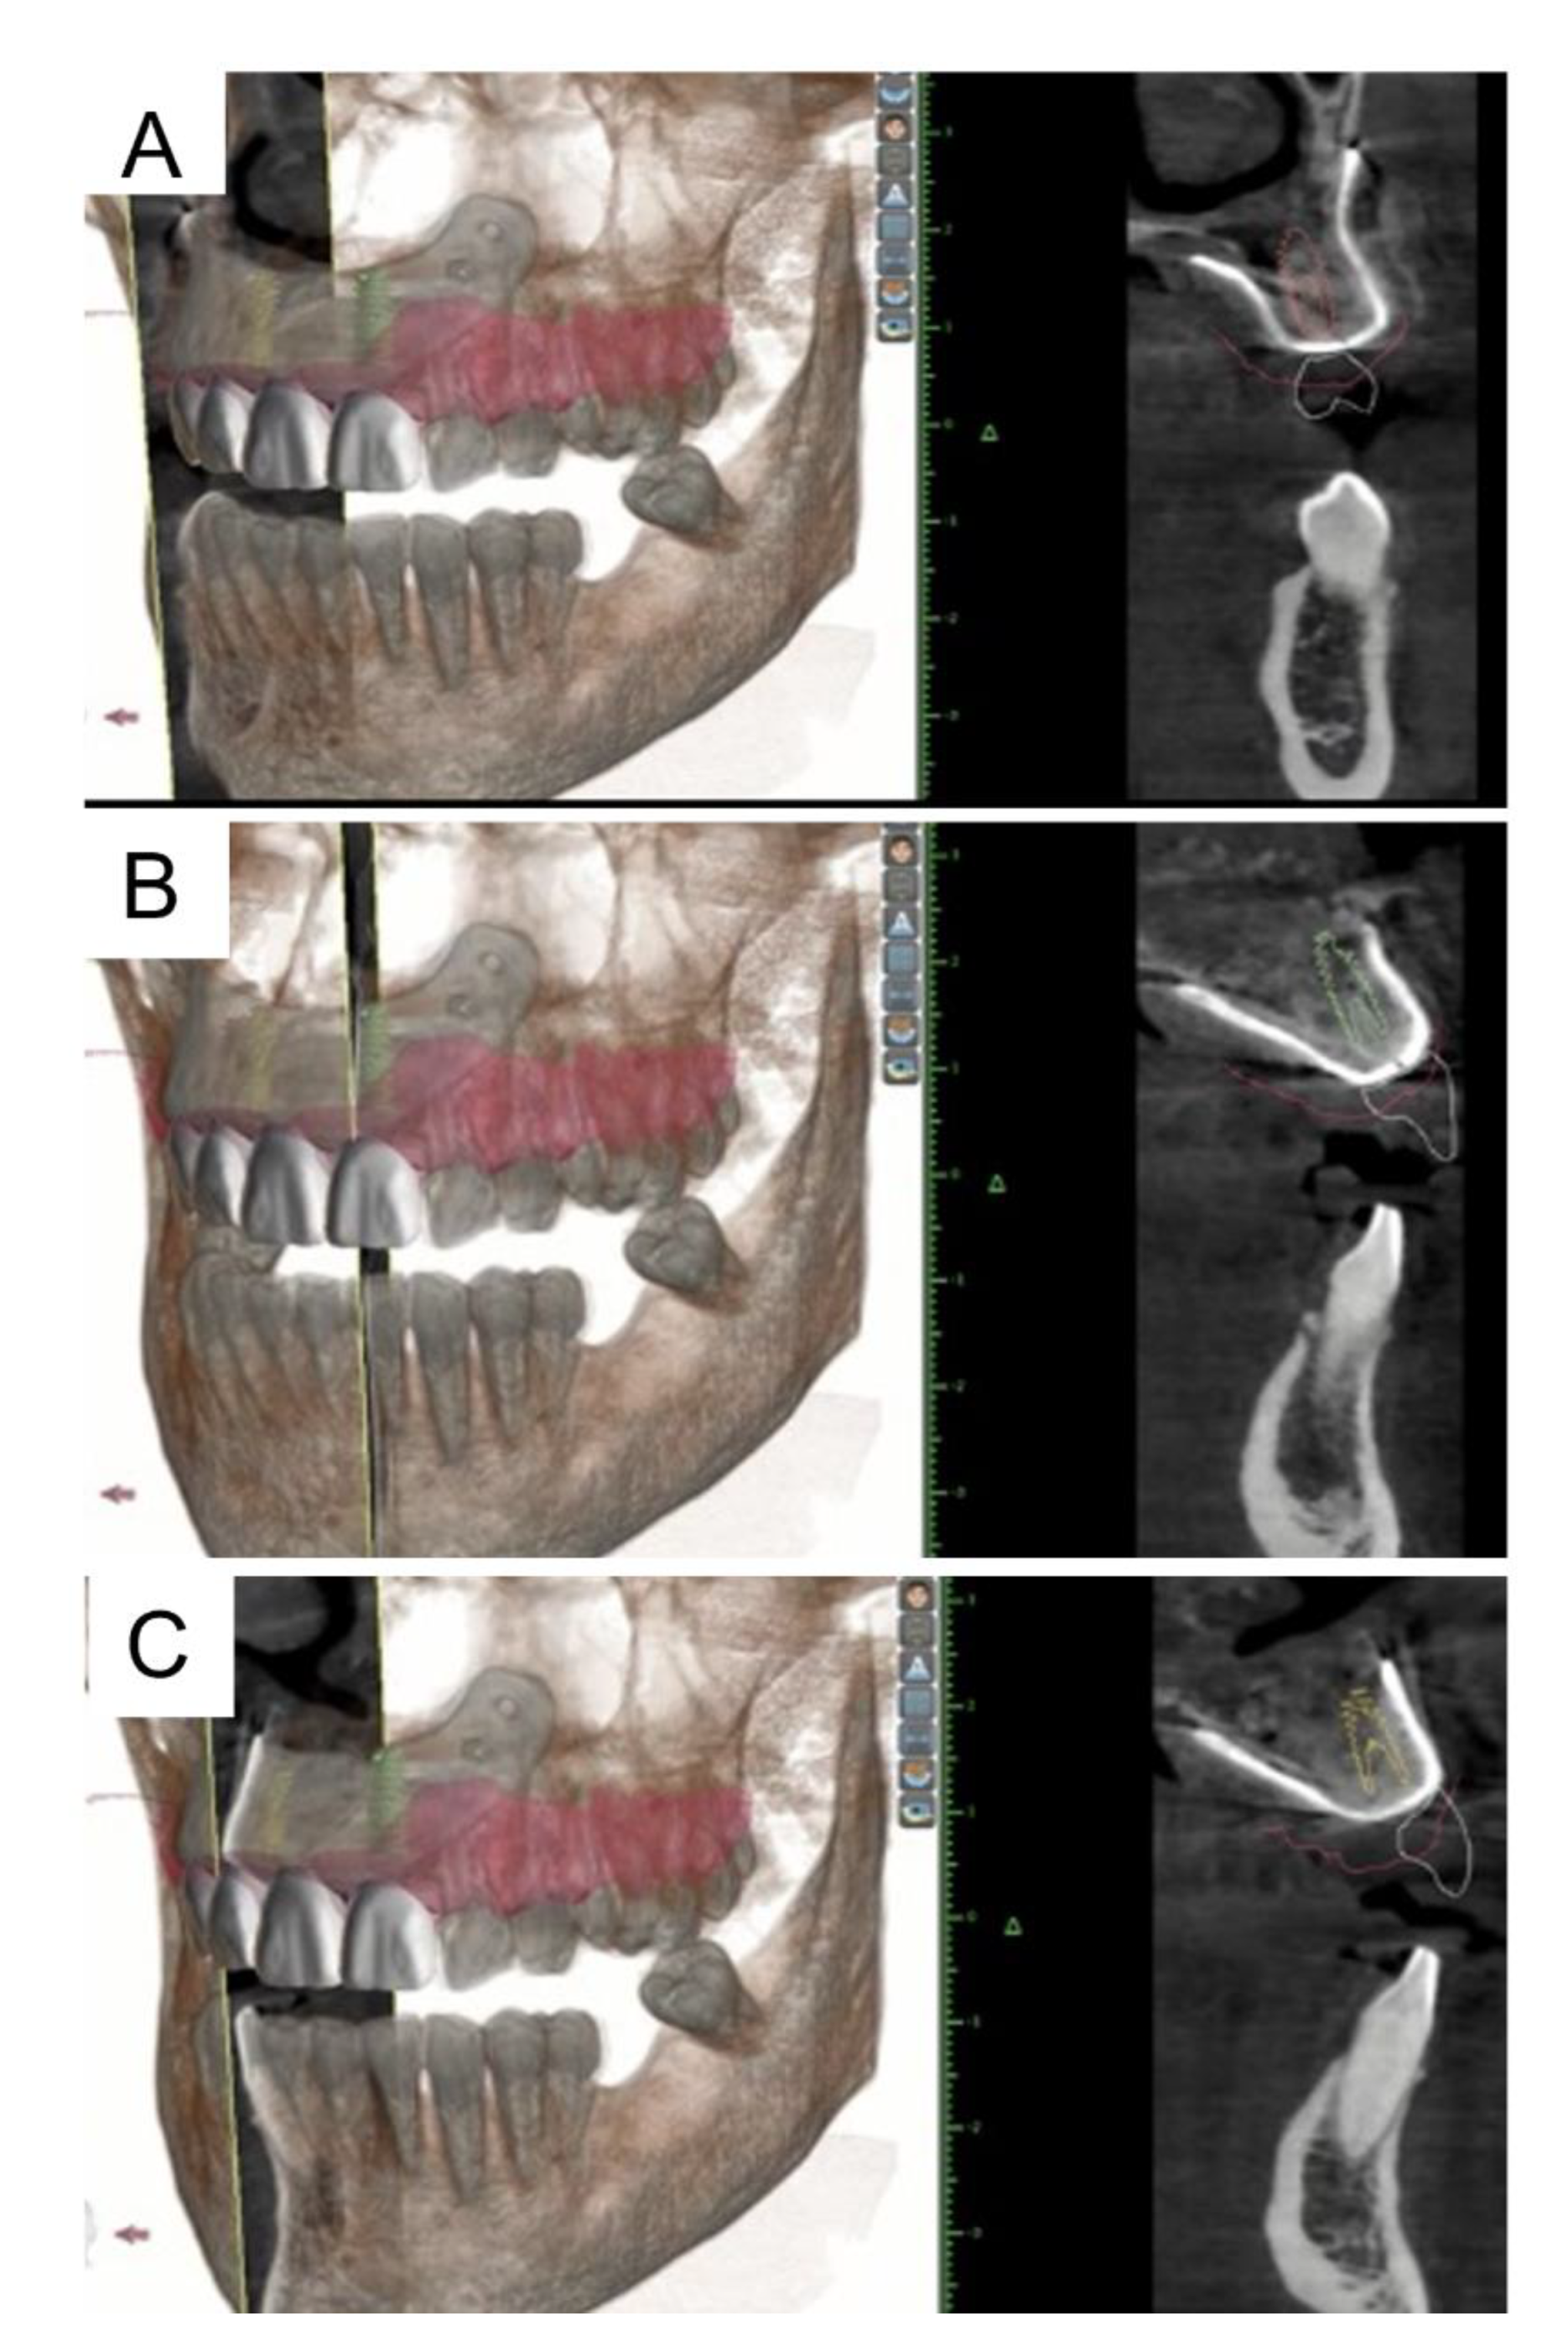

2. Materials and Methods